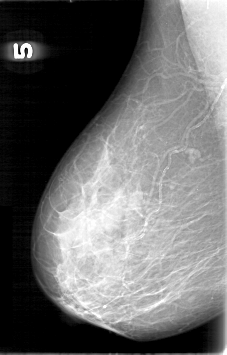

D_4095_1.RIGHT_MLO

RIGHT_CC LINES 4741 PIXELS_PER_LINE 3511 BITS_PER_PIXEL 12 RESOLUTION 43.5 NON_OVERLAY

RIGHT_MLO LINES 5311 PIXELS_PER_LINE 3391 BITS_PER_PIXEL 12 RESOLUTION 43.5 NON_OVERLAY